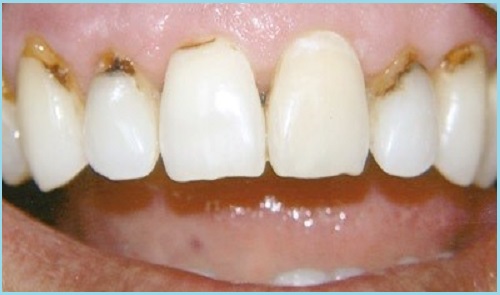

Пришеечный или прикорневой – самая опасная разновидность кариеса, который возникает на зубе в зоне, где он соприкасается с десной и непосредственно – под ней у корневой зоны зуба.